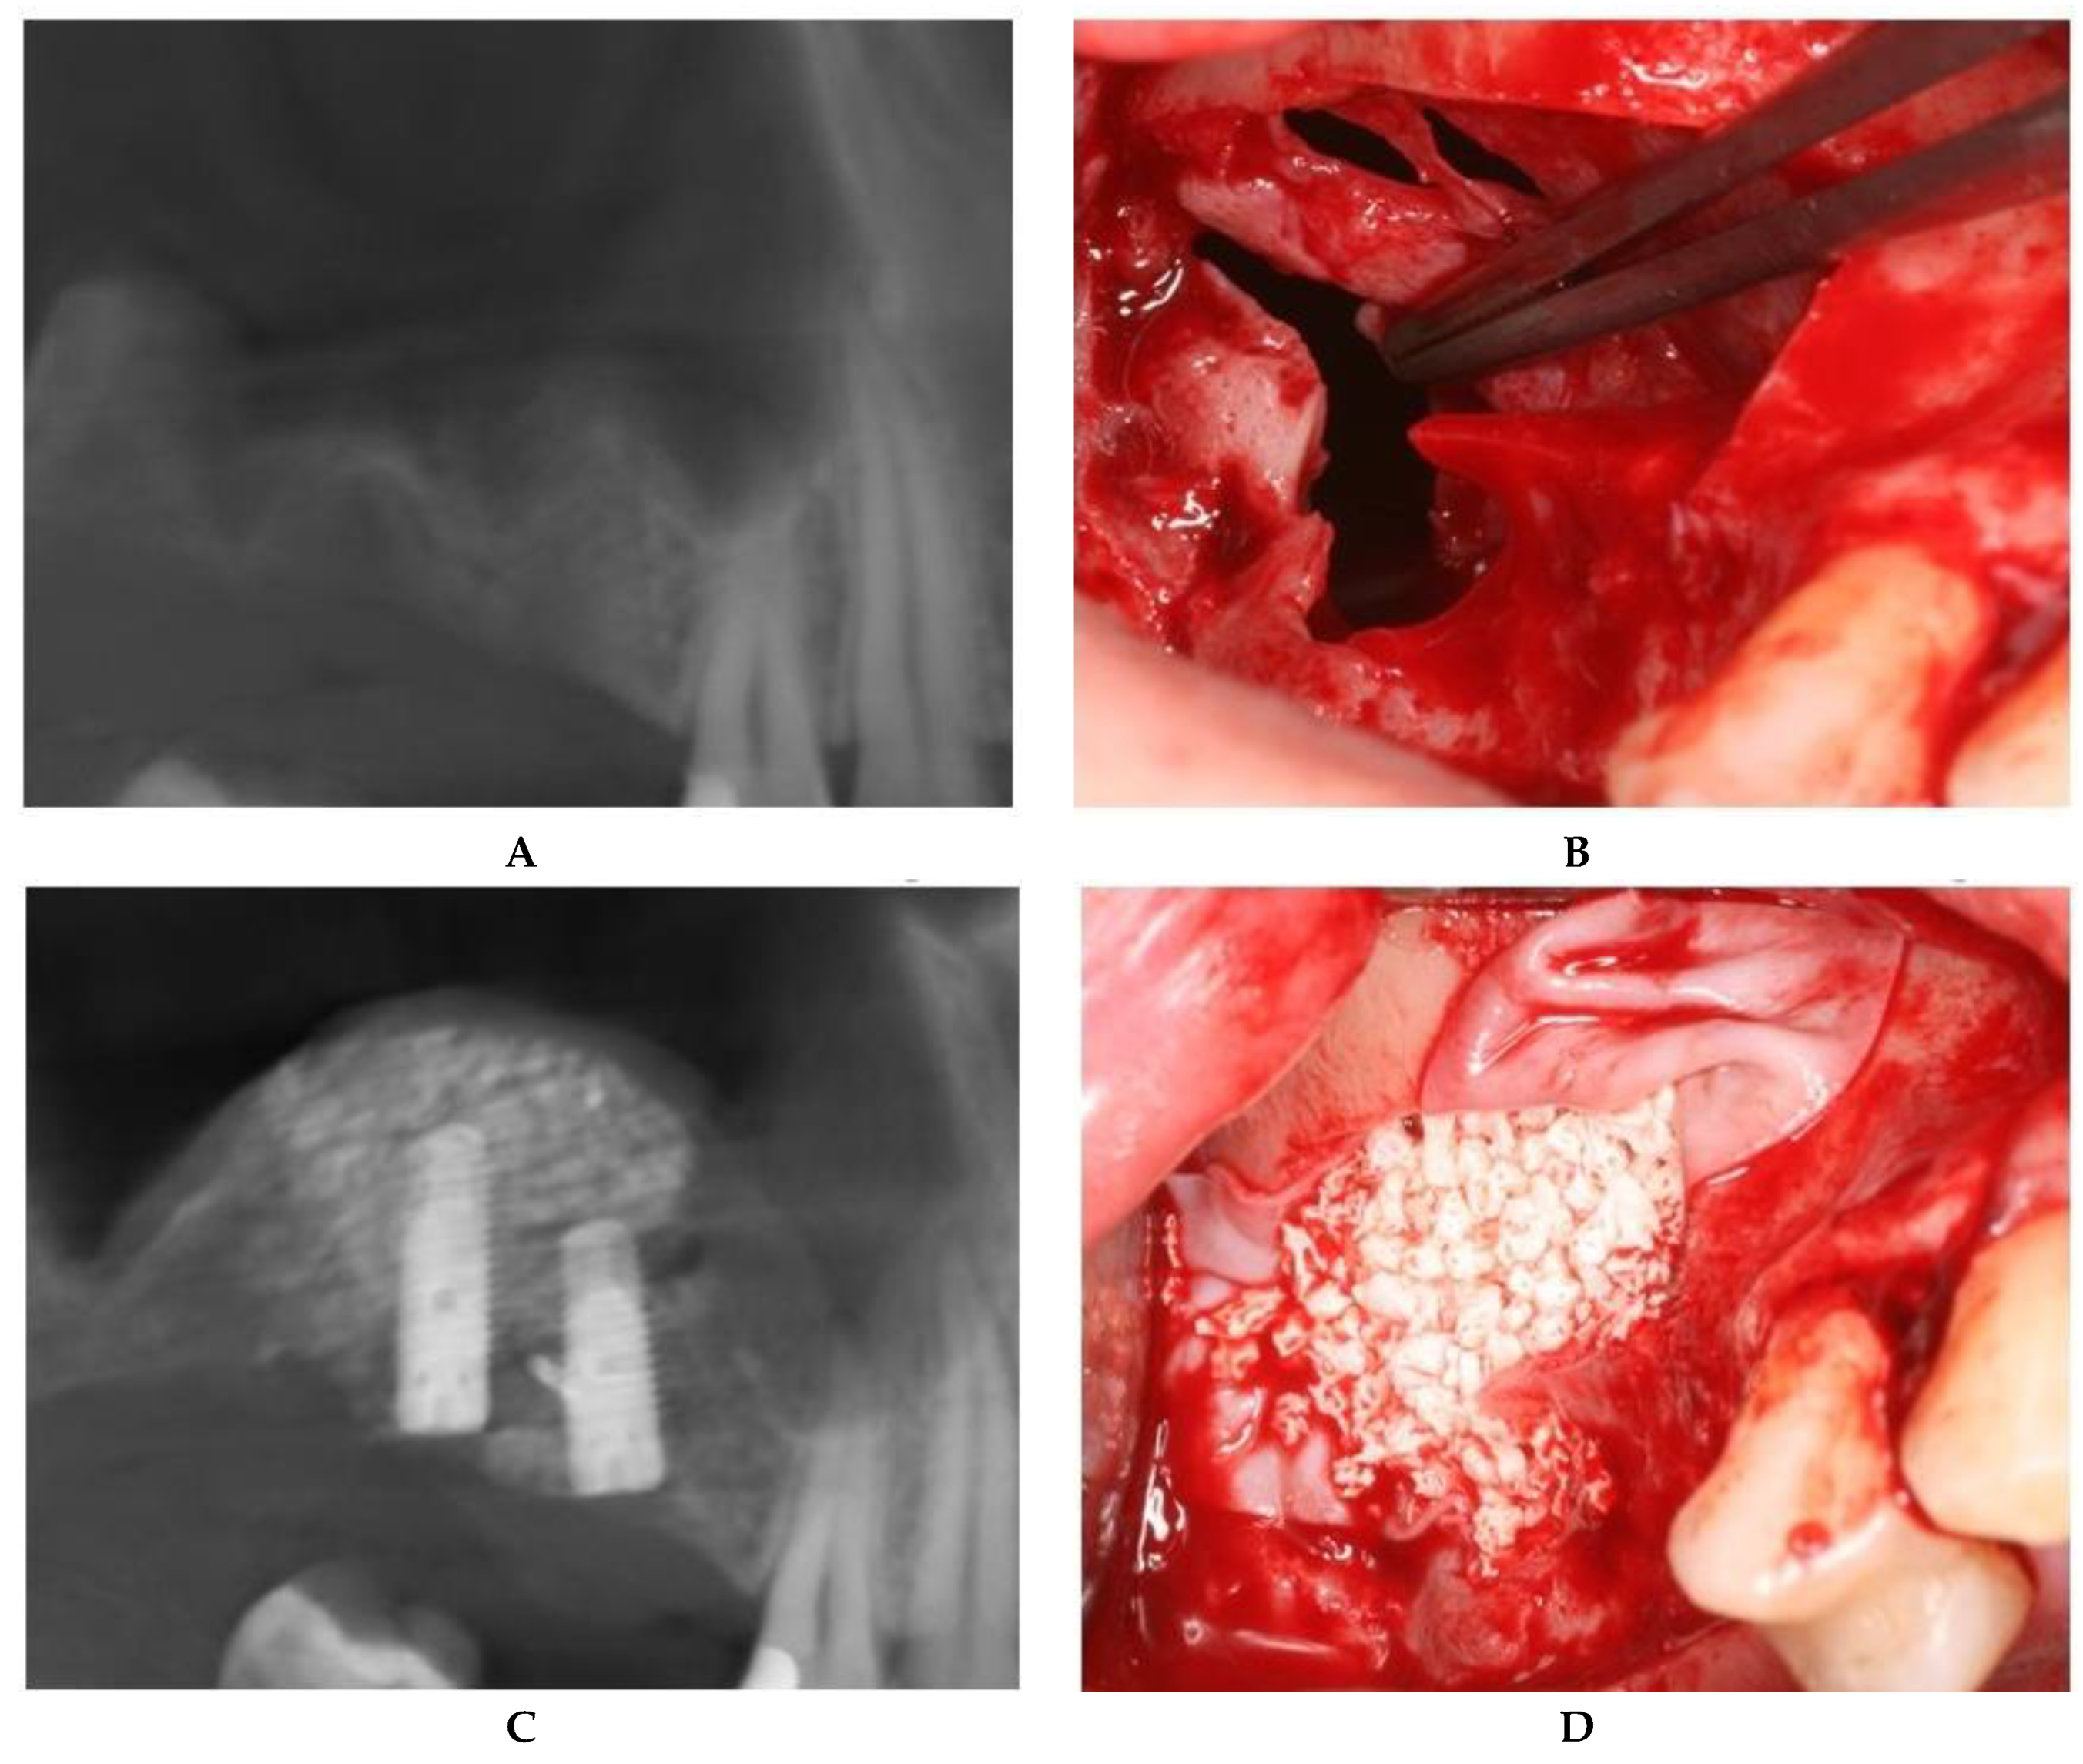

Using a straight handpiece, holes were made in the cortical bone of the lateral wall at the top edge of the window level. To seal the perforation, suturing of the membrane directly to the bony edge was performed using a 6/0 absorbable thread with an 8-mm needle (Figure 3).

Likewise, retractors used to reflect the surrounding tissues located at the upper edge of the access window may cause accidental iatrogenic perforations. Langenbeck and Farabeuf retractors are commonly used for mucoperiosteal flap retraction during oral surgery. The Langenbeck retractor ensures visibility at the surgery site by mechanical traction and reduces hemorrhages by putting pressure on incised tissues [32]. However, incorrect use of these retractors may cause complications such as mucosal perforations, resulting in additional technical difficulties and prolonged surgical intervention. In Figure 3, an iatrogenic sinus membrane perforation is exemplified. Because of muscle fatigue, the assisting physician who retracted the flap to ensure visibility slipped the Langenbeck retractor into the sinus cavity. As a result, membrane tearing occurred at the upper edge of the bone contoured similar to the size of the retractor.

Figure 3. Iatrogenic perforation produced with a Langenbeck retractor. (A) Perforation located at the superior edge of the osteotomy. (B) Preparation of the holes in the bone. (C) Suture of the mucosa to the superior bony edge. (D) Postoperative panoramic image after implant placement.